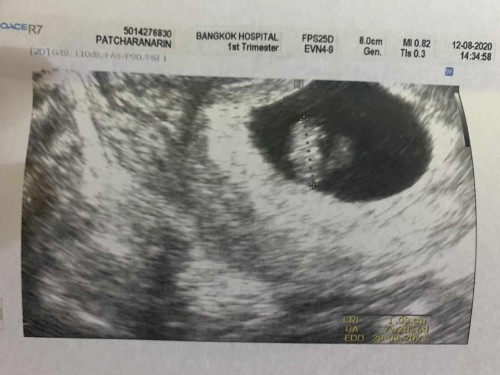

ภาวะแท้งคุกคาม 7+4 week มีน้ำสีน้ำตาลปนเลือดนิดหน่อย ไปหาหมอฉีดยากันแท้งให้ ลูกหายใจปกติดี คุณแม่ช่วยแนะนำหน่อยนะคะ กังวลใจมากๆเลย#ท้องแรก